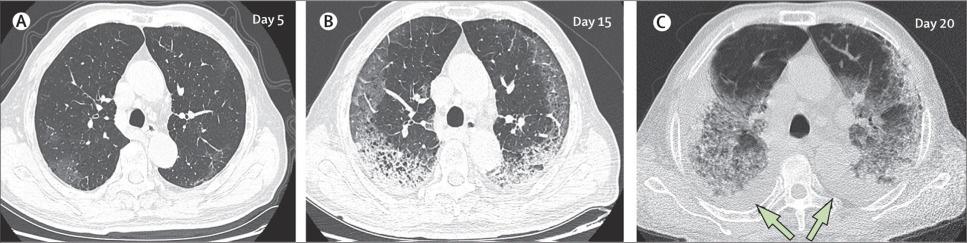

Đây là CT phổi của một bệnh nhân nam 77 tuổi (ở Trung Quốc) trong gần 3 tuần điều trị. Đáng tiếc, tình trạng của bệnh nhân nguy kịch, không qua khỏi do sức tàn phá mạnh của virus bên trong phổi. (A) - ngày thứ 5, sau khi khởi phát triệu chứng: các mảnh mờ đục bắt đầu loang lổ, ảnh hưởng đến nhu mô phổi hai bên, dưới màng cứng. (B) - ngày thứ 15, các đốm trắng hình lưỡi liềm đã chiếm lấy cả hai phổi, xuôi theo võng mạc phía sau và tập trung ở đáy. (C) - ngày 20, các tổn thương mở rộng ra hai bên phổi, đốm trắng gần như chiếm được cơ quan này và xuất hiện tình trạng tràn dịch màng phổi hai bên (mũi tên). 10 ngày sau lần quét này,bệnh nhân tử vong. Ảnh: The Lancet.